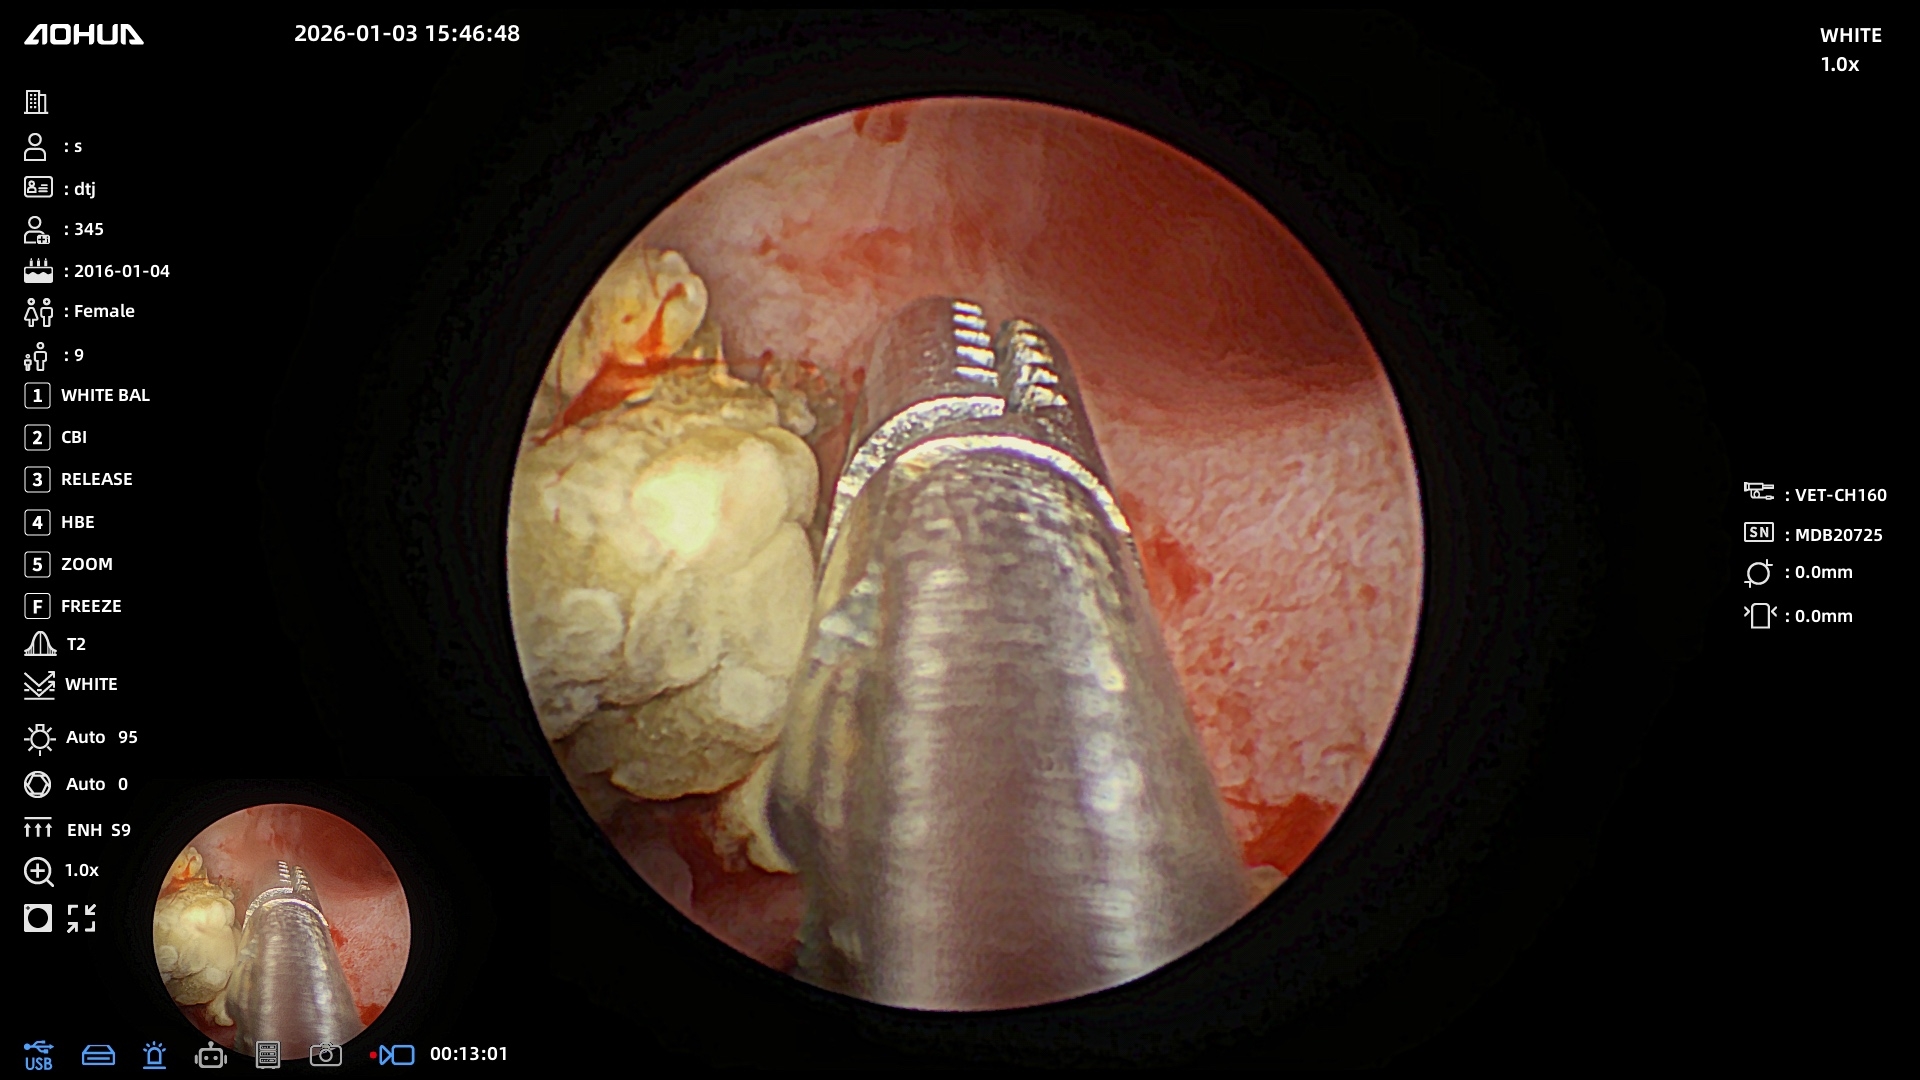

Нас тепло приняли в Эндовет, провели все необходимые обследования и на следующий же день была назначена операция. Нашей таксе почти 10 лет, опасались, как она перенесет наркоз. Но после беседы с Александром Владимировичем стало спокойнее. Операция длилась 3 часа, были удалены камни из почек и мочеточника, установлены стенты. Все прошло более чем хорошо. 2,5 дня стационара, 2 небольших прокола, собака чувствует себя хорошо и быстро восстанавливается. Большое спасибо команде клиники, анестезиологу, работникам стационара, регистратуры и, конечно же, Александру Владимировичу за такой тяжёлый и нужный труд. До сих пор не верится, что мы дома и все закончилось благополучно благодаря Вам)